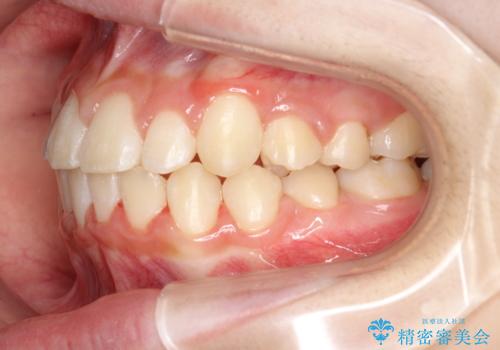

矯正歯科治療 → 叢生(でこぼこ・八重歯)

インビザラインによるガタつきの矯正治療 シンプル・短期間

犬歯のねじれ 下の歯のがたがた インビザラインで

前歯のがたがた 前歯が内側に傾いている

前歯がガタガタ・噛み切りにくい インビザラインによる歯を抜かない矯正

前歯が八重歯でガタガタ ワイヤーによる抜歯矯正